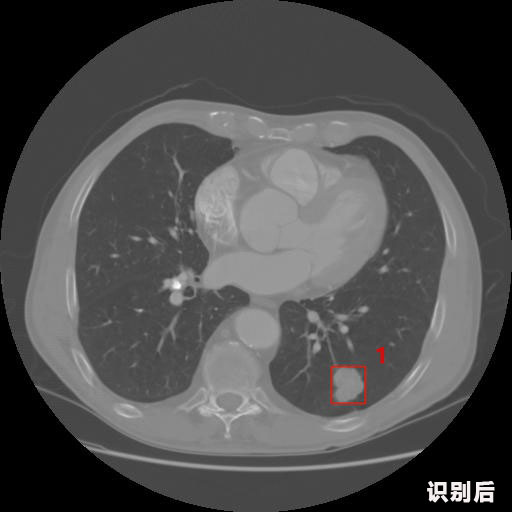

英特健康A(chǔ)I深度學(xué)習(xí)醫(yī)療圖像識(shí)別系統(tǒng)案例_胸部CT

1.發(fā)現(xiàn)肺結(jié)節(jié)的可能性為95.56%---位于框指數(shù)位置:[331.70554 366.13406 365.21707 403.96234]